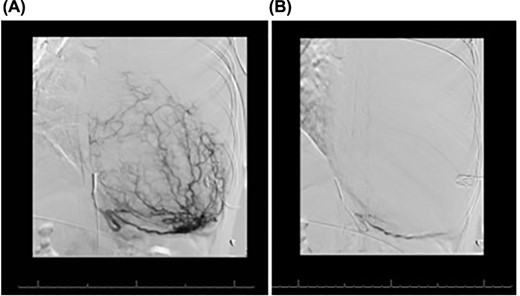

Magnetic resonance imaging showed no invasion of chest wall or visceral structures, consistent with resectability (Fig. 2). To prepare for resection, thoracic aortography showed 75% of tumor arterial supply from left inferior phrenic artery, which was subsequently coiled with particles (500 μm and 700 μm embospheres) (Fig. 3A). Postembolization arteriogram demonstrated near complete cessation of anterior flow within this vessel and its branches (Fig. 3B).

(A) Conventional angiogram engaging the left inferior phrenic artery, which perfuses much of the mass. (B) Postembolization results, demonstrating marked decrease in the mass blood supply.